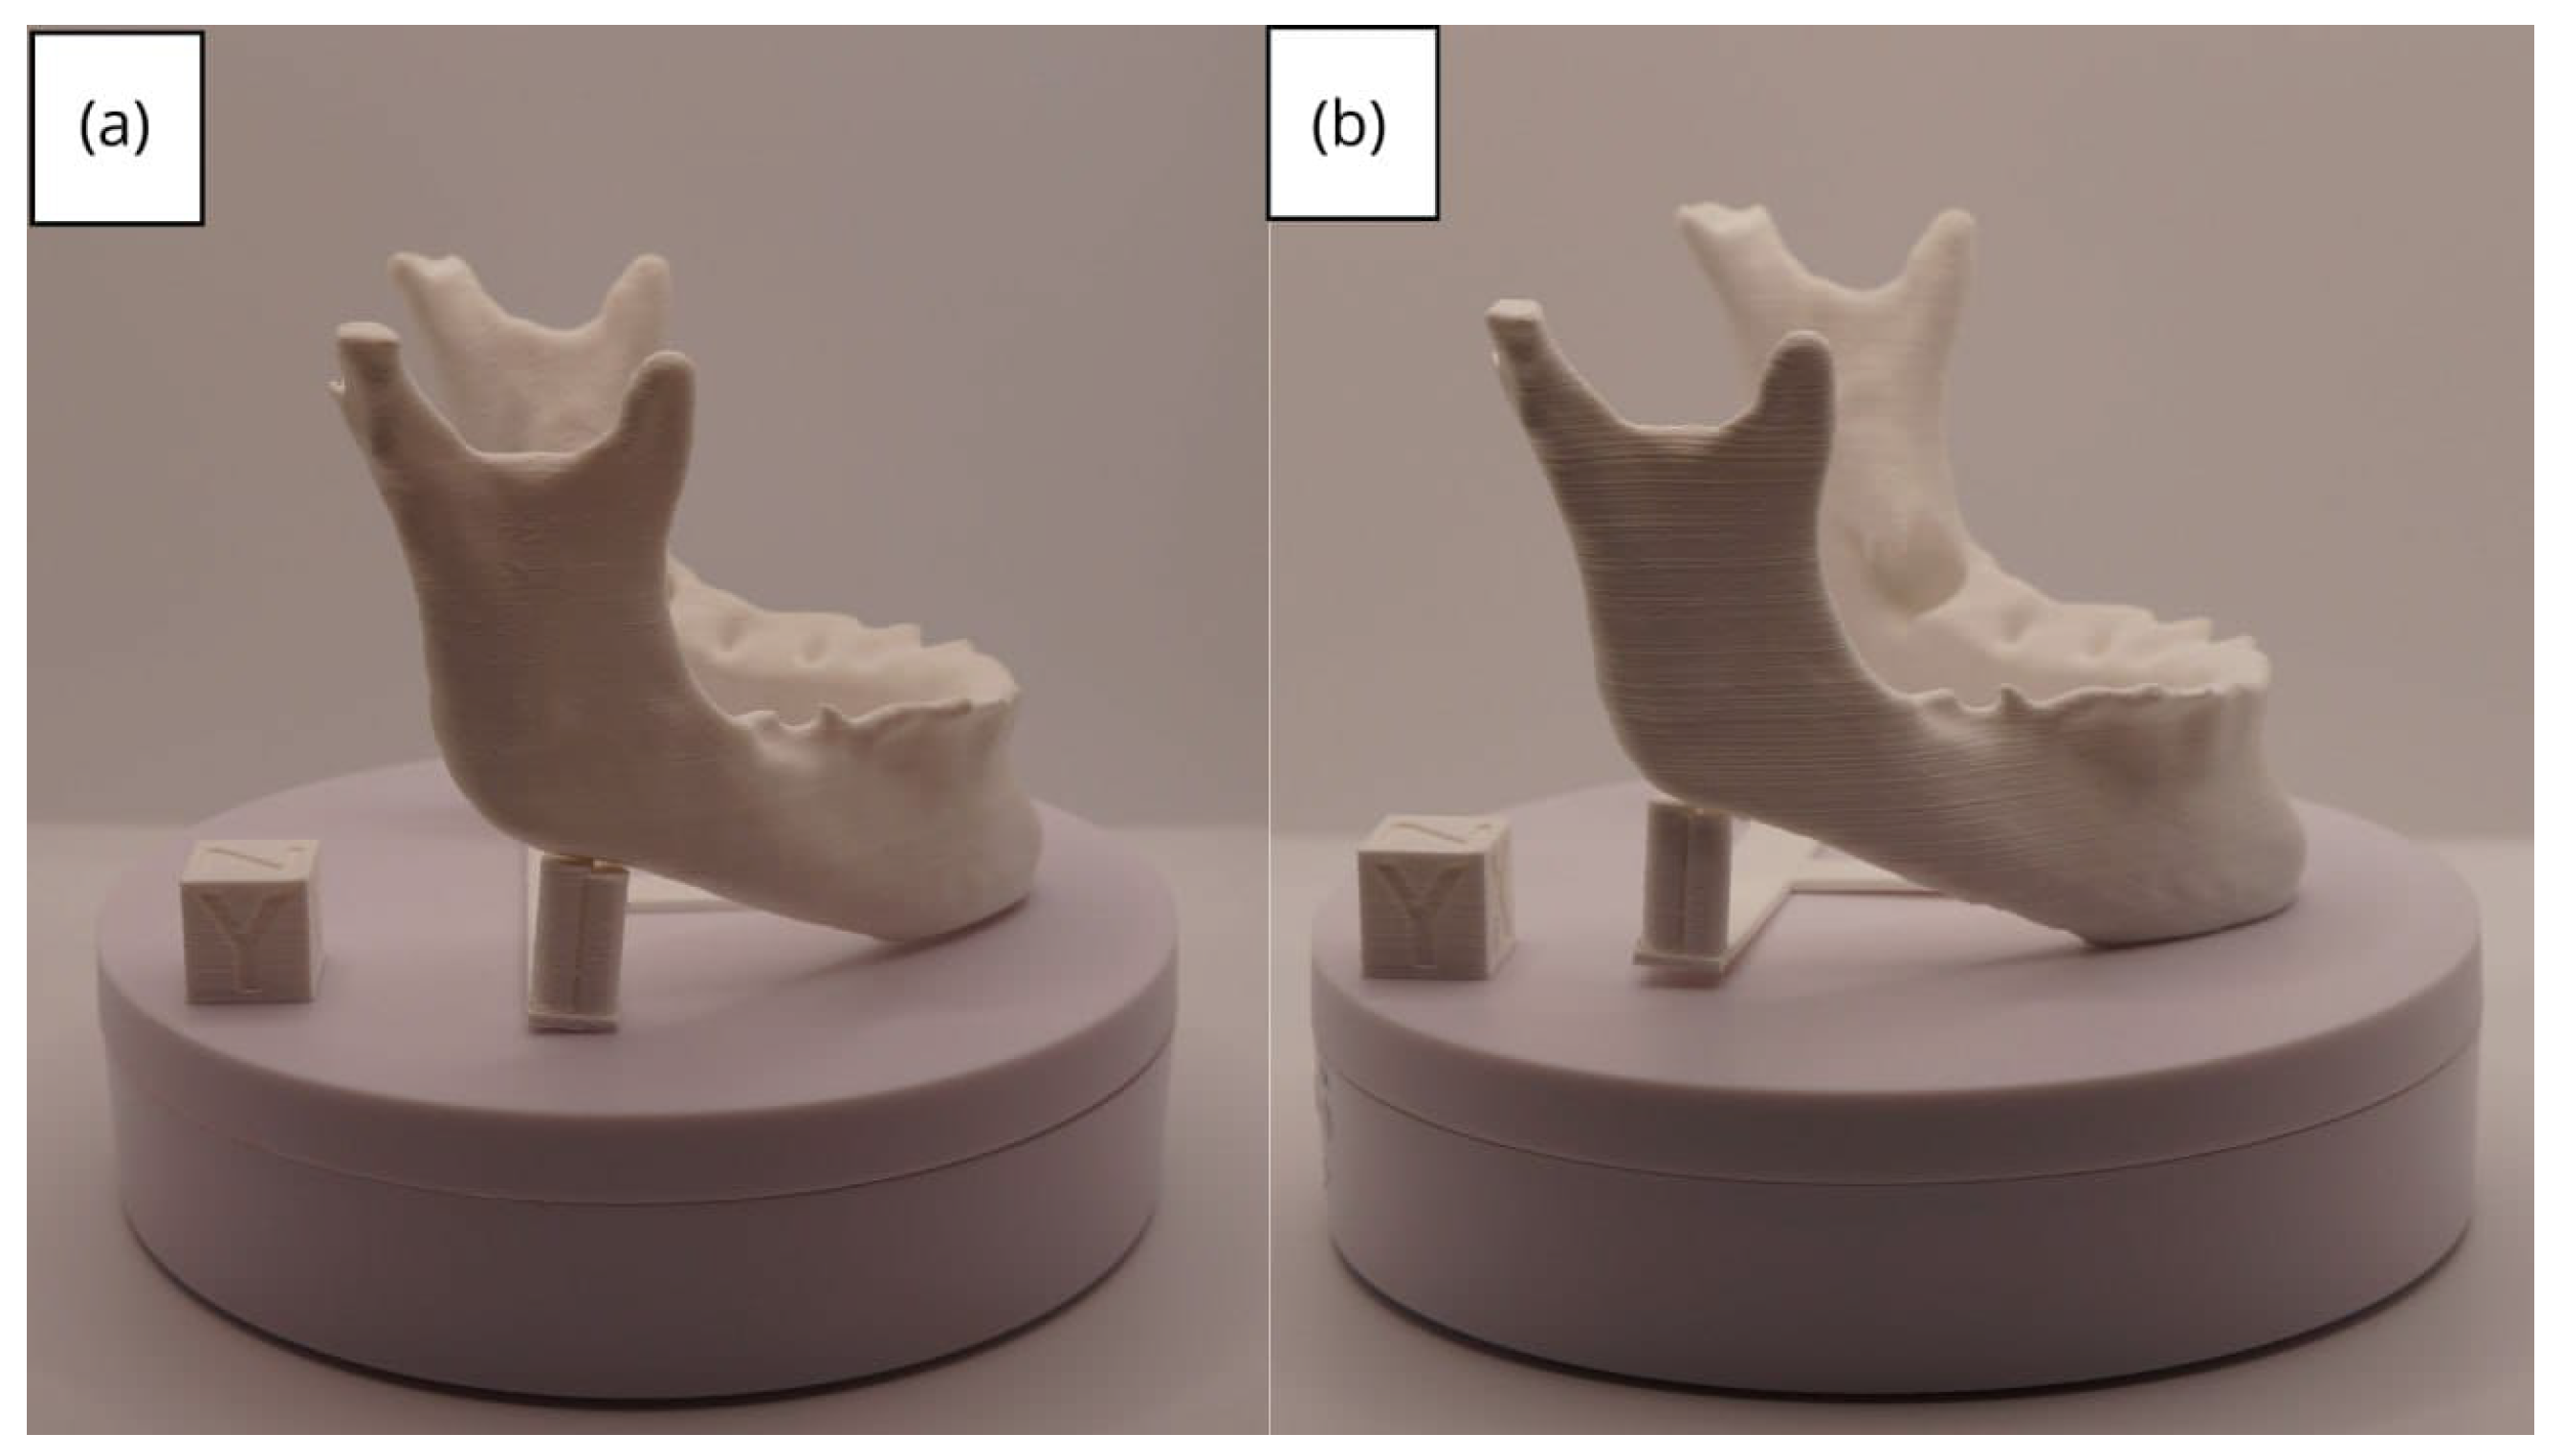

3.2. Human Lower Jaw

3.2.1. DICOM-to-STL Files

3.2.2. STL-to-GCODE Files

3.2.3. Final Printing

| Lower jaw models | m; m | Artillery Sidewinder X2 |

| m; m | Creality Ender 3 | |